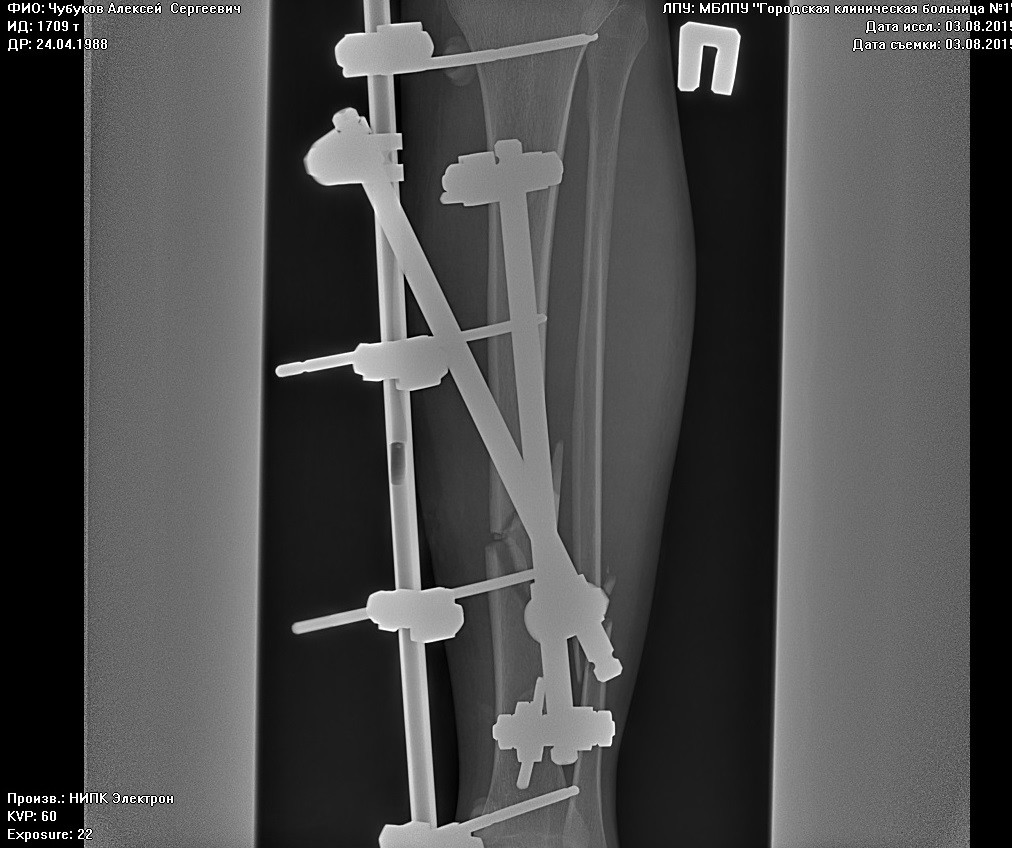

Вот такая конструкция теперь красовалась в моей ноге) В этот же день хирург пришел на осмотр, сказал, что можно вставать на костыли и давать нагрузку ноге до 20 кг. Плюс было назначено физиолечение (магнит), лечебная гимнастика.

А вы в такие малые сроки ничего и не увидите! Перелом голени в самых хороших случаях срастается за 3,5-4 месяца. Можете посмотреть мои снимки (пост выше), там даты есть. Я тоже задавал врачам вопросы по поводу малоберцовой кости, мне сказали не беспокоиться, всё срастется. хотя меня тоже гложут сомнения по этому поводу. А снимки у вас есть? Костная мозоль при пульпации прощупывается?